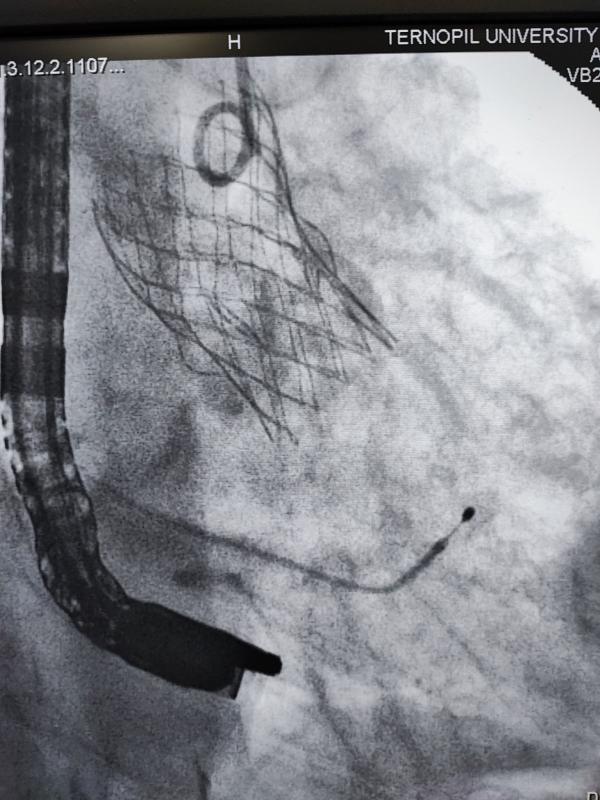

У Тернопільській обласній клінічній лікарні вперше виконали складну операцію на серці — транскатетерну імплантацію аортального клапана через трансапікальний доступ. Для медиків це унікальна операція, про її результати розповів лікар Богдан Маслій.

— Суть операції полягає в тому, що на працюючому серці виконується невеликий отвір, через який через трубку-катетер по провіднику вводиться згорнутий клапан, — пояснив Богдан Маслій. — Позиціонування контролюється як рентгенівським зображенням так і черезстравохідним ультразвуковим датчиком. Після імплантації хірург затягує вузол навколо отвору і ушиває рану. Крововтрата є мінімальною.